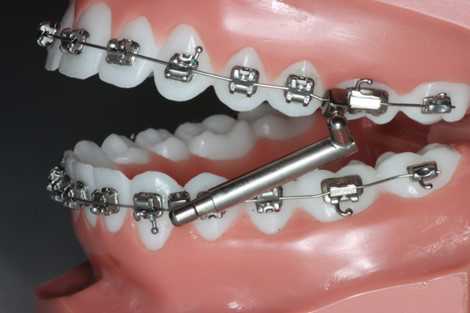

Faste sektioner, der limes på tænderne og hjælper underkæben frem ved hjælp af teleskopstænger.

De bruges sammen med faste bøjler.

Bruges ved stort overbid.

Sidder fast på buerne i overkæben og underkæben, og hjælper underkæben frem.